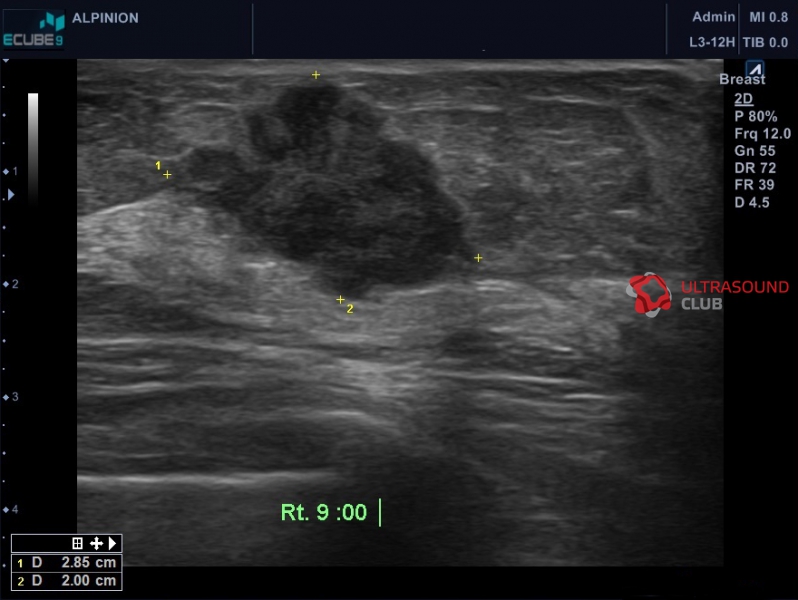

Одна из пациенток обратилась к врачам по поводу образования в молочной железе. Ей поставили диагноз «фиброаденома», назначили гормональные препараты. При этом ни цитологическое исследование, ни консультация онколога не проводились. Через три месяца, когда новообразование увеличилось в размере, женщина обратилась в другую медицинскую организацию, где ей назначили биопсию и направили к онкологу.

Вместе с тем, некоторые злокачественные опухоли можно спутать с доброкачественными. Например, если диагностические обследования провели некачественно, можно перепутать доброкачественную фиброаденому со злокачественной медуллярной карциномой груди. Поэтому, если результаты исследований вызывают у вас сомнения, обратитесь к другому специалисту за вторым мнением.